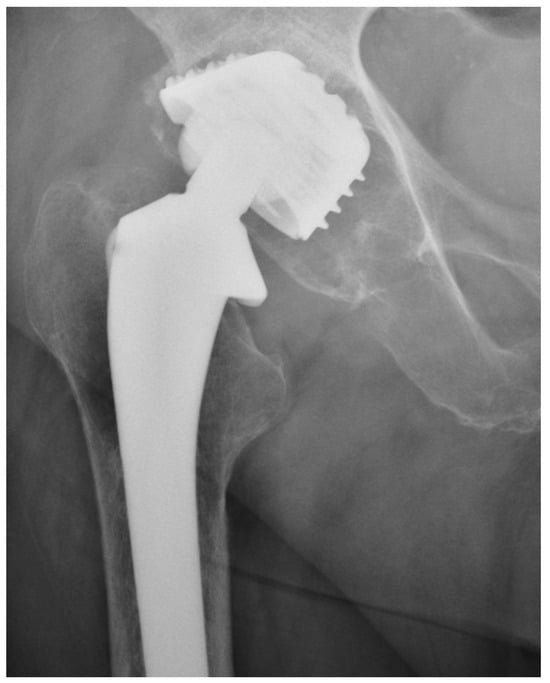

We observed a positive correlation between the increase in the mean oxidation index (OI) of the bearing surface of the inlays and the extent of periacetabular osteolysis classified according to the Paprosky scale (R = 0.44; p = 0.011). The most commonly revised types were 3A and 2B: 12 out of 33 samples (36.36%) were classified as type 3A, and 7 out of 33 samples were classified as type 2B (21.21%) according to Table 2. Mean oxidation index values for each type are, respectively, presented in Table 3. Figure 1 illustrates the differences in oxidative indices between the control sample and selected samples from groups 1 and 3B. Attention should be paid to the difference in the spectrum range of 1685–1745 cm−1. Representative X-ray images of patients depicting the extent of osteolysis based on the Paprosky scale can be seen in Figure 2, Figure 3 and Figure 4.

Figure 3. Periacetabular osteolysis classified as Paprosky 2B.

Figure 4. Periacetabular osteolysis classified as Paprosky 3B.